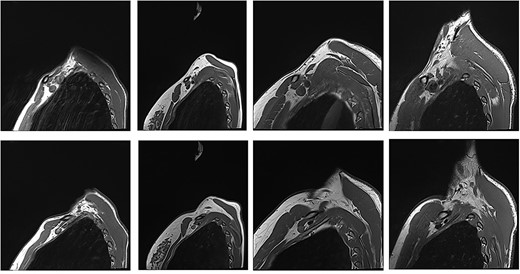

Unaffected patients. The top row are sequences with the arm in the neutral position. The bottom row is the corresponding patient with the arm raised.

Patients with nTOS. The top rows are sequences with the arm in the neutral position. The bottom row is the corresponding patient with the arm raised.

With the arm elevated, there is narrowing of the costoclavicular space between the posterior border of the clavicle and anterior border of the first rib (Figs 1 and 3). In unaffected patients, there is a small amount of fat that persists around the cords of the brachial plexus with the arm elevated (Fig. 2). In our series, we considered a patient to be positive for nTOS if there is loss of the perineural fat signal demonstrating that the nerves are in direct contact with the posterior border of the clavicle and anterior border of the first rib (Fig. 1b).